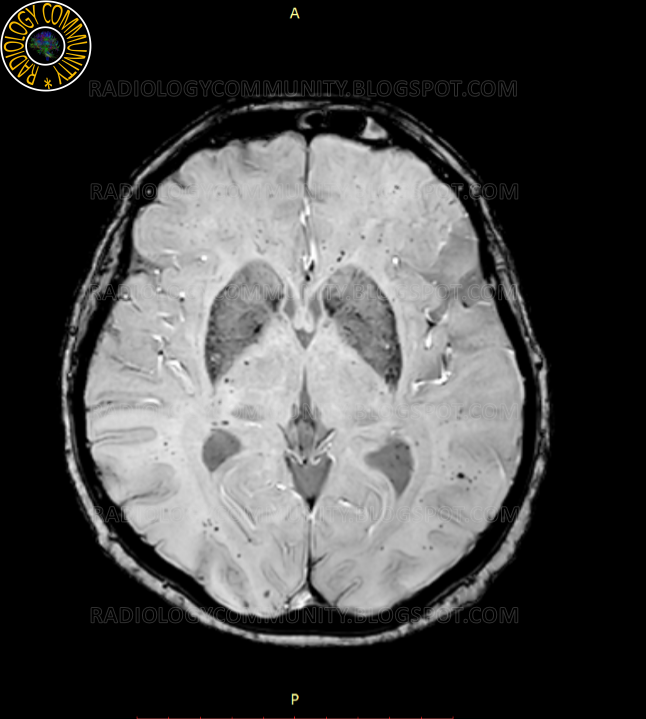

Artefact σε ακολουθία ASL (Arterial Spin Labelling)

Όπως είναι φανερό τίποτε το

περίεργο αναφορικά με την ποιότητα των εικόνων δεν επισημαίνεται στις εικόνες

α) έως και ε). Παρόλα αυτά το ASL (εικόνα στ)

αναδεικνύει

μια «εκτεταμένη» ισχαιμία στο αριστερό εγκεφαλικό ημισφαίριο. Το εύρημα αυτό

δεν είναι συμβατό με καμία από τις άλλες εικόνες που λήφθηκαν.

Ο καθετήρας ακινητοποιήθηκε

(δεν μπορούσε να απομακρυνθεί) όσο το δυνατόν μακριά από το πηνίο. Η ακολουθία ASL επαναλήφθηκε

και ιδού το αποτέλεσμα…